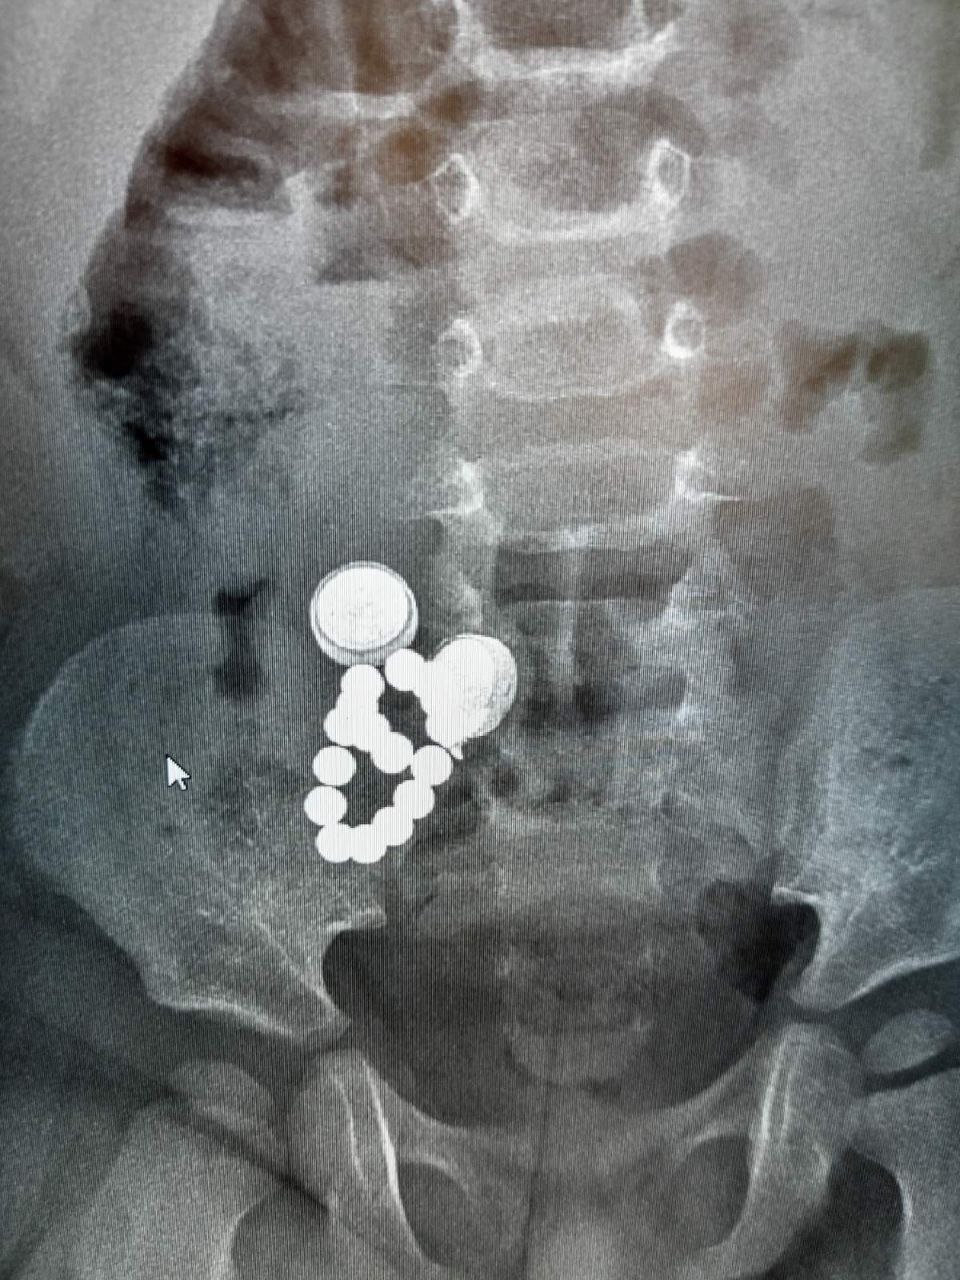

Проглатывание магнитных шариков

Батарейки круглые в желудке